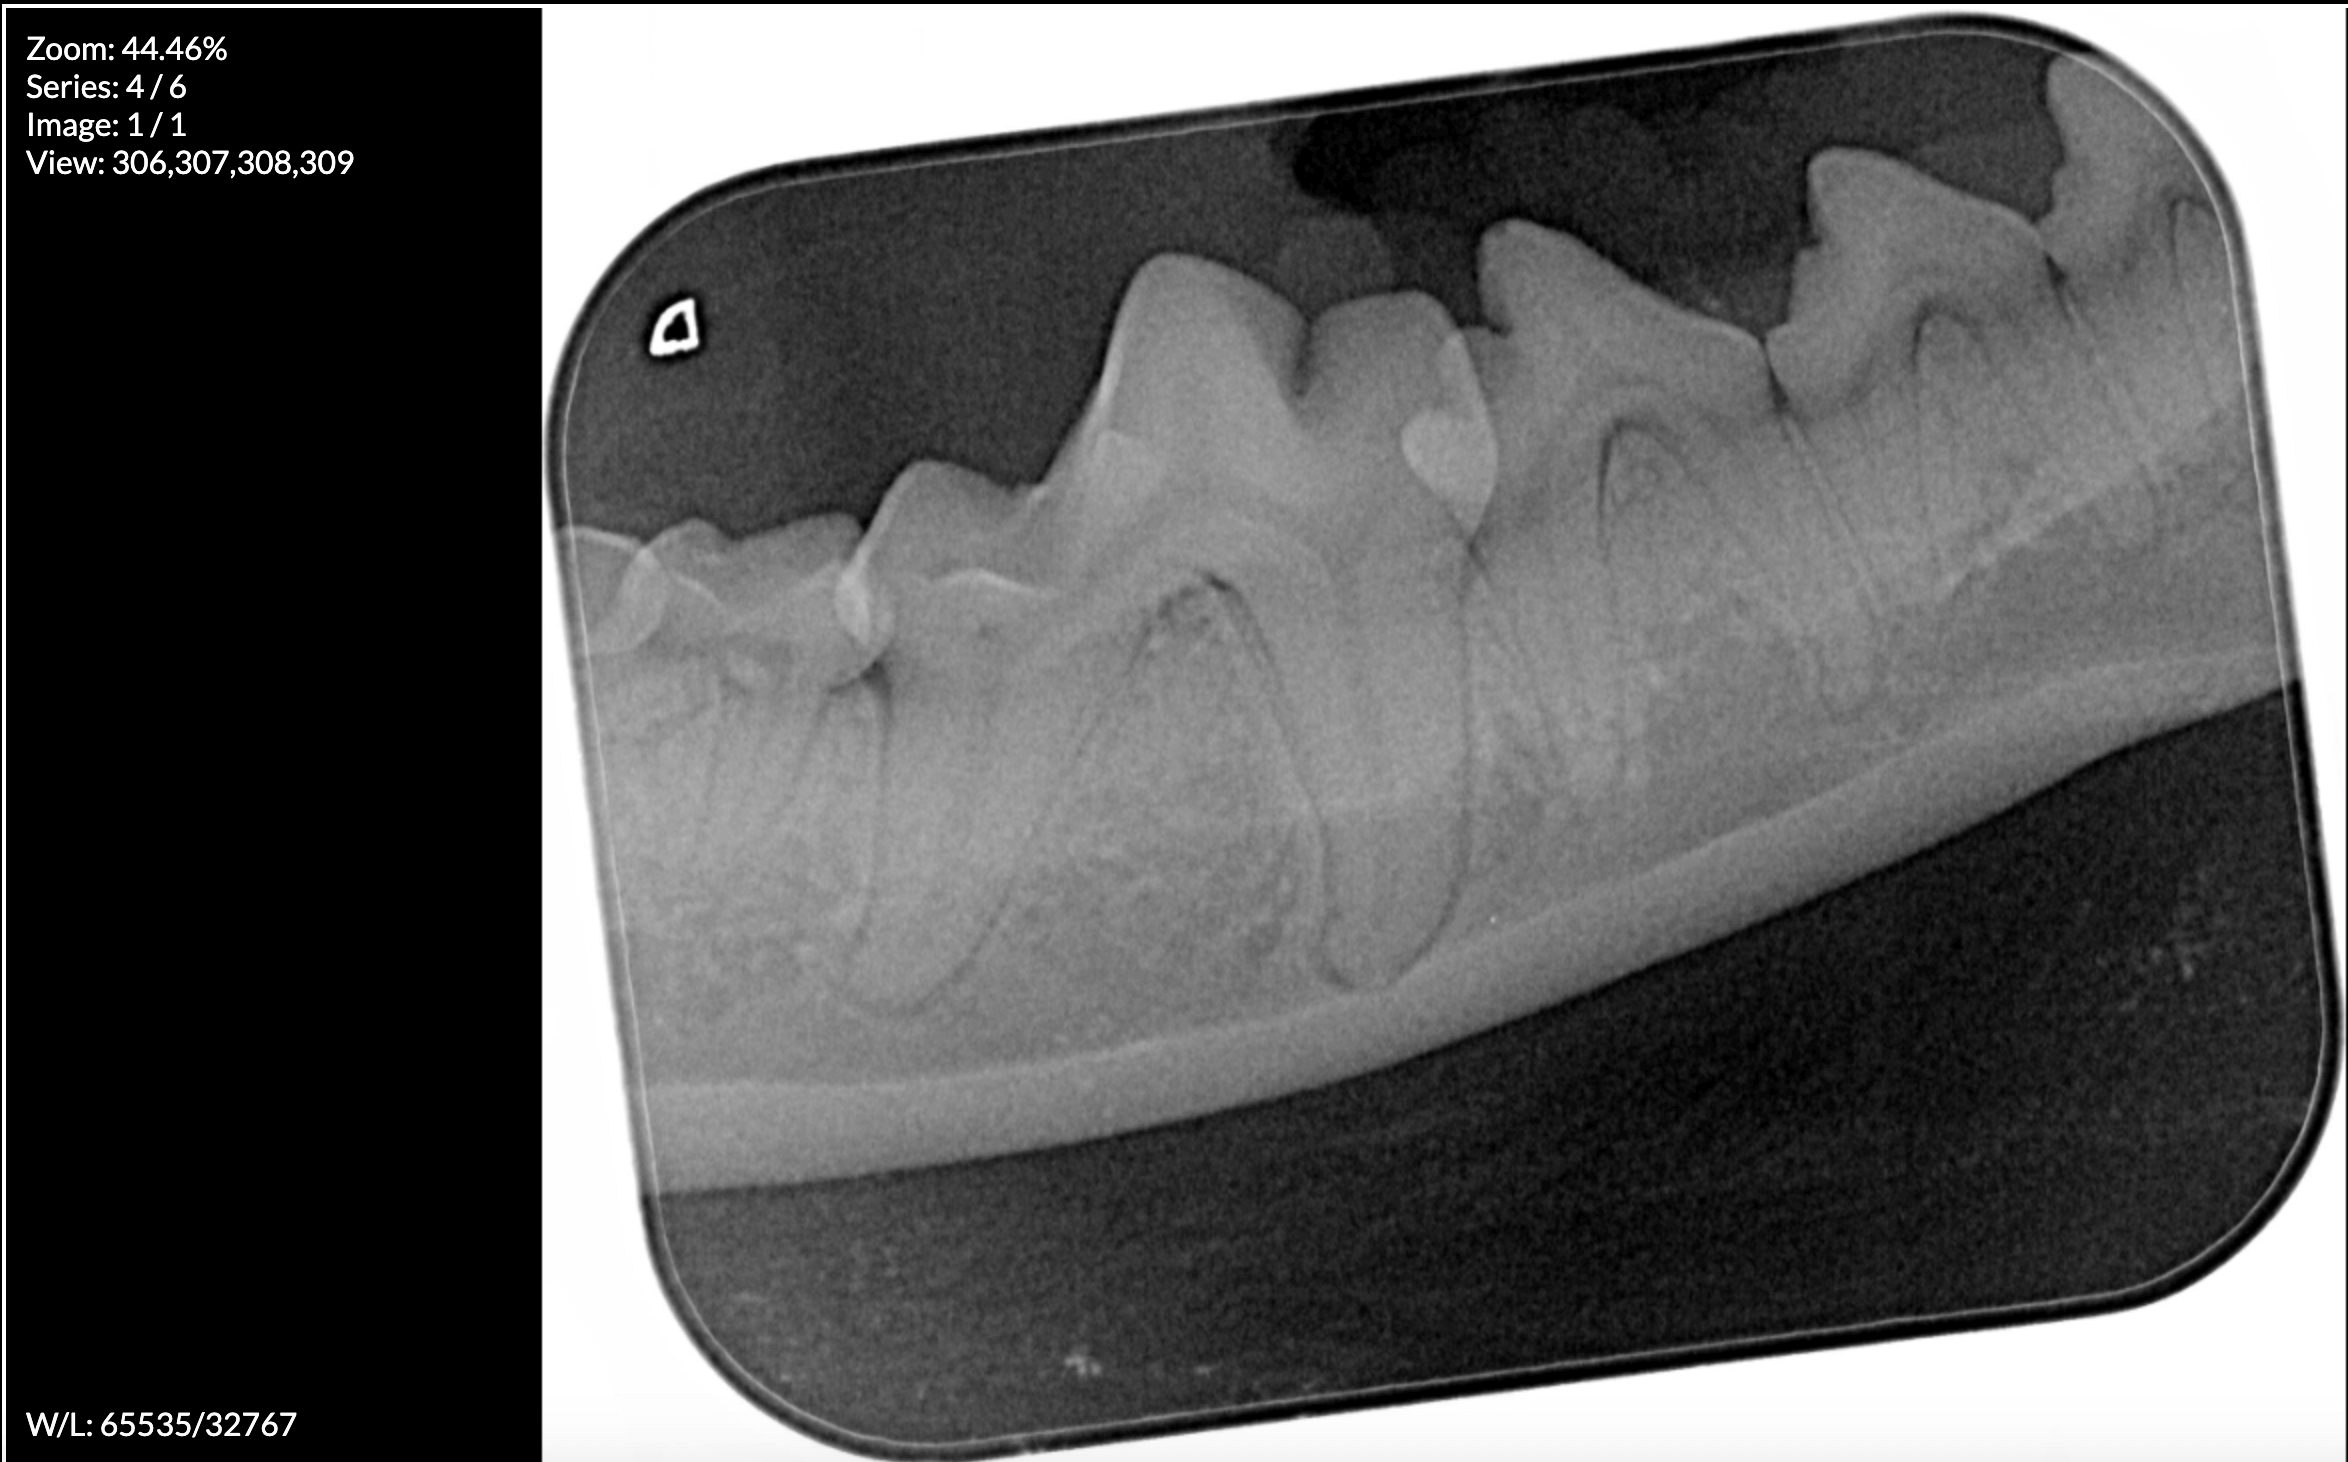

The Floreat Vet is fully equipped to carry out dental surgery on site. With our full suite of IM3 dental equipment, including the atraumatic VetTome and a state of the art Dental XRay machine, we prioritise the safety and comfort of your cat or dog while addressing their dental concerns.